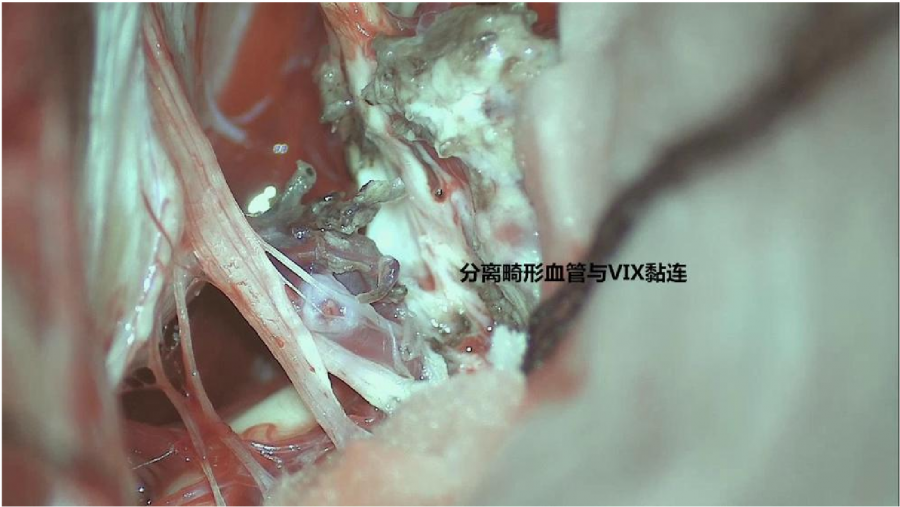

⾏左侧远外侧⼊路脑⼲⾎管畸形切除术,术中所⻅:

术后患者轻度⾯瘫House-Brackmann分级III级,可恢复。

3、脑⼲动静脉畸形⼿术切除是注意辨别供⾎动脉与引流静脉,其往往不似其他部位的动静 脉畸形,有叫粗⼤的引流静脉。术中如果不能辨清各⾎管来源与去处,往往会造成不可估量的损失。